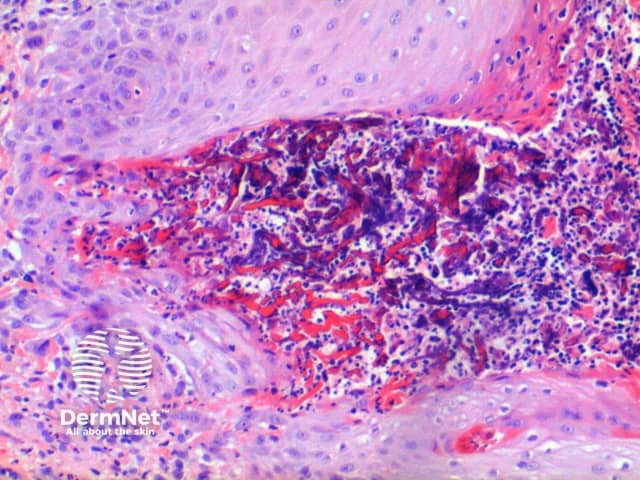

Low power of histology of elastosis perforans serpiginosa demonstrates a column of keratotic debris forming a focal invagination through a hyperplastic epidermis (figure 1). Closer inspection identifies material undergoing transepidermal elimination (figure 2). Brightly eosinophilic fibres are seen within the extruded material, mixed with keratinous debris and a mixed inflammatory cell infiltrate (figures 3, 4).

Figure 3